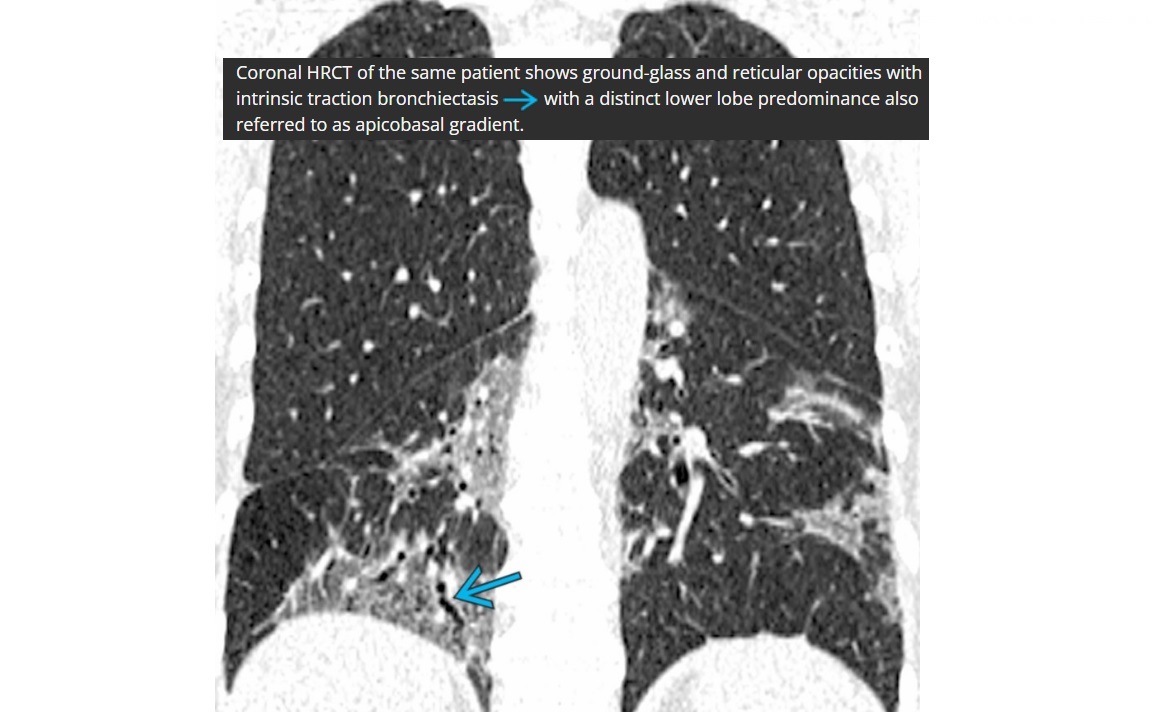

NSIP

lower lung zone predominant

CT

Absent (less) / microcystic honeycombing

Bilateral ground-glass &/or reticular opacities

Traction bronchiectasis/bronchiolectasis

Relative Subpleural sparing

peribronchovascular fibrosis